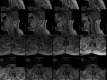

Figure 4. Pathologic staining of the tumor

(A) H&E staining shows dense lymphohistiocytic proliferation with no atypia or mitotic figures identified. (B) CD68 immunostaining reveals diffuse positivity reflecting a mononuclear infiltrate characteristic of giant cell tumors. (C) H&E staining shows multinucleated giant cells (red arrow) along with pigment-laden macrophages (black arrow) H&E: hematoxylin and eosin